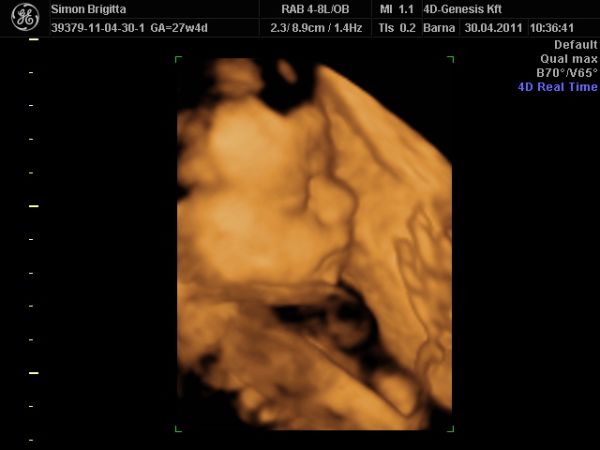

Már nagyon fáradt vagyok, de mindenképpen be akartam jelentkezni, mert ma voltunk a 4D Genesisbe és az étteremben is.

Először természetesen az ultrahangról: annyira szuper volt újra látni a kiscsajt, merthogy még mindig puncis szerencsére :lol:

Most készített a szonográfus 2D-ben néhány igazi "hamburger" fotót!

Teljesen egészséges, fejvégű, mindene rendben van, a méhlepény még mindig mélyen tapad, magzatvíz átlagos, lepény 0. fokban érett.

És legnagyobb meglepetésemre nagyobb a "koránál", a buksija alapján 29+1, az adatok átlaga alapján 28+5 (ténylegesen pedig 27+4).

Becsült súlya 1220 gramm!

Ami a legnagyobb élmény volt nekünk: egy az egyben úgy néz ki, mint Luca a 32. heti 4d-s ultrahangon anno! Hihetetlenül hasonlítanak egymásra!